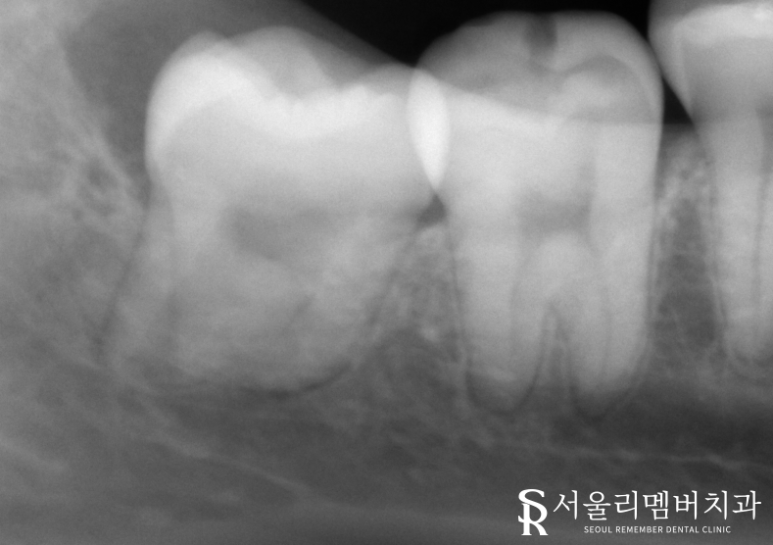

확인을 위해 Panorama와 CT 촬영을 하였습니다.

사랑니가 잇몸 속에 숨어 있는 매복 상태 였습니다.

뿌리 끝이 하치조 신경과

굉장히 가깝게 위치해 있었습니다.

잇몸을 열고 치아를 쪼개

하치조 신경관이 다치지 않게 조심히 발치하였습니다.

발치 후에 남은 치아 조각이 없는지

확인하기 위해 X-RAY 촬영을 하였습니다.

남은 조각 없이 깨끗하게 발치된 모습입니다.